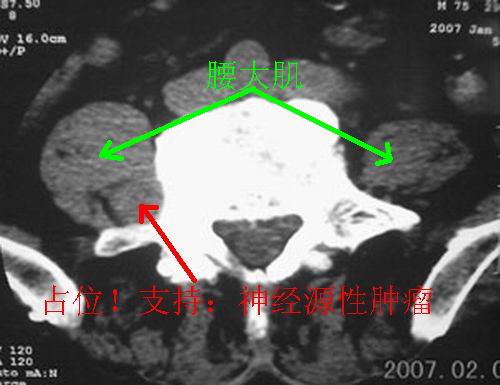

男,75岁,腰周疼5-6年。别无症状。

1.神经源性肿瘤(良性)可能性大;

考虑神经源性肿瘤可能大。依据:右侧神经孔扩大,相应部椎体压迫吸收。建议增强扫描,或mri平扫+增强。t1呈低等信号,t2呈高信号。增强后病灶(+++)强化。病灶内常见坏死。

右侧椎旁、侧隐窝软组织肿块,呈不规则双极征改变,椎体后外缘骨质弧形压迹,椎间孔扩大;考虑神经源性肿瘤,神经鞘瘤可能性大,需与神经纤维瘤相鉴别。